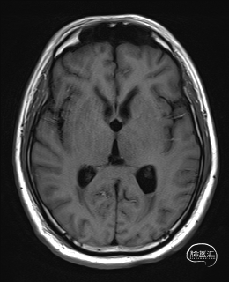

5.术后72小时复查磁共振提示海绵状血管瘤全切。

术后72hMRI复查

2.术后面部麻木及右上肢麻木明显缓解,出院时仅右手指麻木;

3.头痛等颅高压症状缓解;复视无明显缓解;

4.无新发神经功能障碍;